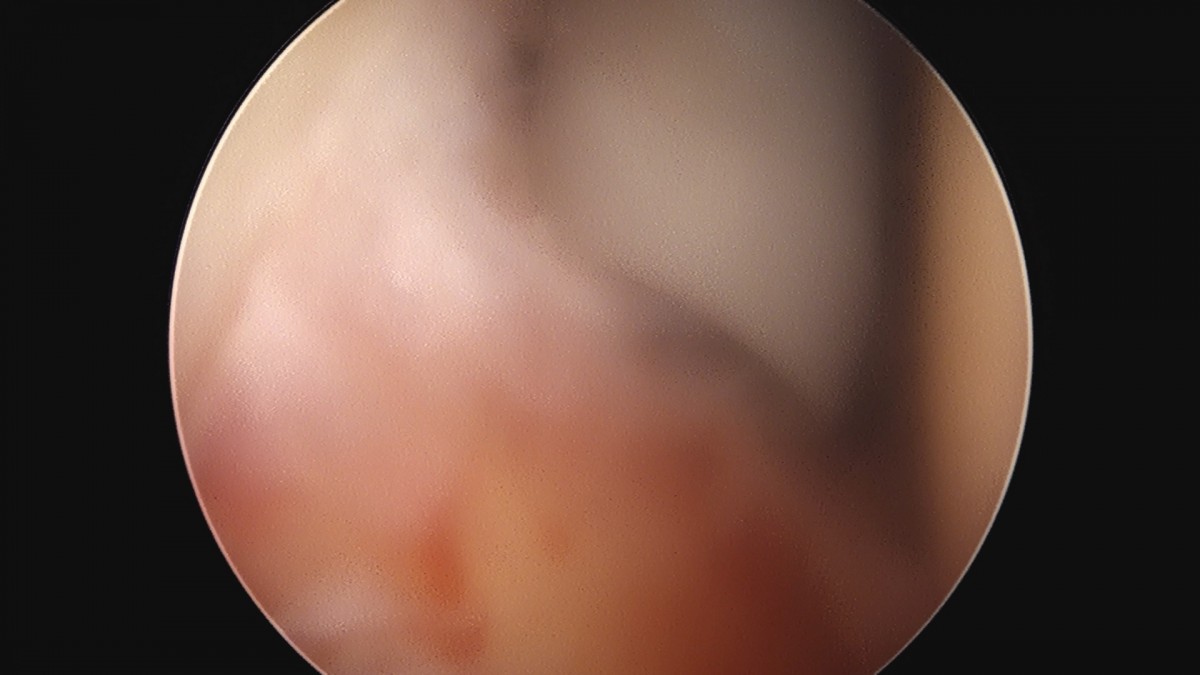

이재상원장님 어깨 견봉하 감압술 김선O 환자

dae765e4d9ac96aee867c9d6292d8784_1758004048_8969.jpg